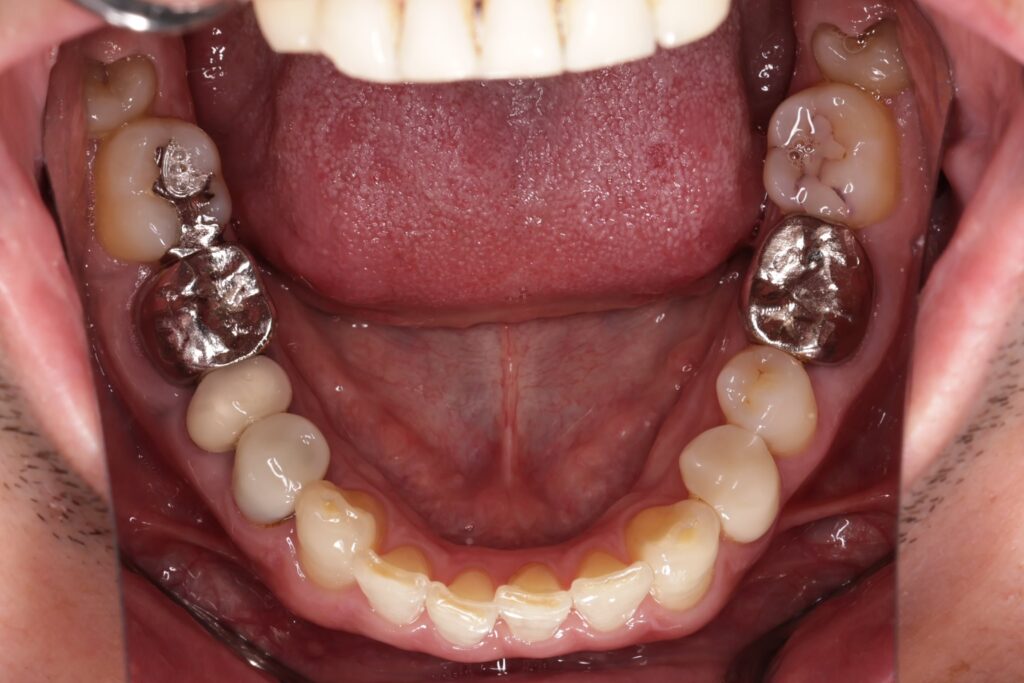

初診時の口腔内の状態:

口腔内には多数の銀歯(銀合金)が確認されました。患者様は過去に多くの虫歯治療を受けており、そのほとんどが保険適用内の銀合金で修復されていました。

Before